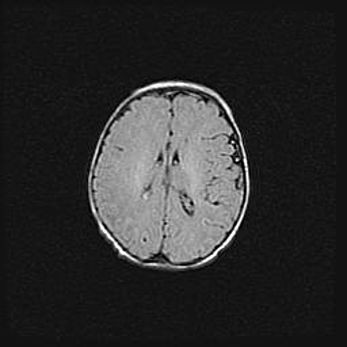

Церебральная ишемия II.

Возраст: 7 дней

Вес: 3350 г

Пол: женский

Окружность головы: 35 см

Срок гестации: 39 недель

Ишемия головного мозга – это состояние, которое развивается в ответ на кислородное голодание вследствие недостаточного мозгового кровообращения. У новорожденных она является следствием дефицита кислорода, что ведет к метаболическим расстройствам различной степени тяжести в тканях головного мозга, в том числе к развитию коагуляционных некрозов и гибели нейронов.